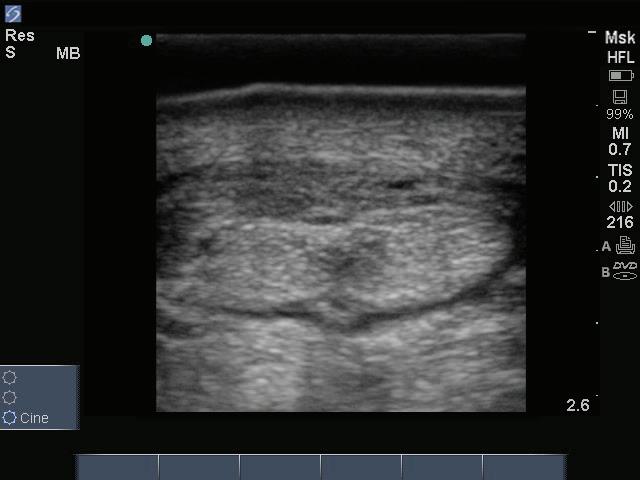

Fig. 6: Ultrasound images of a right fore palmar pastern that was palpation demonstrating a lesion in the right straight distal sesamoidean normal left pastern is on the left.

Figure 6: Ultrasound images of a right fore palmar pastern that was mildly thickened on palpation demonstrating a lesion in the right straight distal sesamoidean ligament. The normal left pastern is on the left.

Image courtesy of Dr. Richard D. Mitchell.